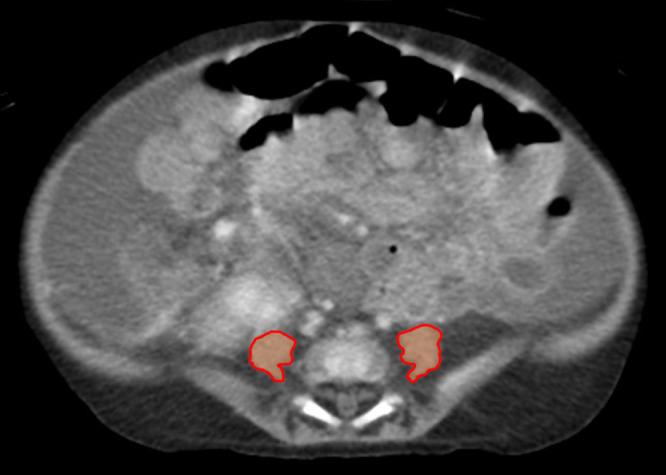

Sarcopenia, a pathologic deficiency of muscle mass and function, has emerged as an important secondary feature of many chronic disease states. For adults with end stage liver disease, there are multiple mechanisms which contribute to sarcopenia and its presence has proven to be an important predictor of morbidity and mortality. In children, there are only a limited number of reports which investigate the role of sarcopenia in liver disease. These studies, which are discussed and summarized in this review, report small, single-center analyses with dissimilar study cohorts and varying clinical definitions. Still, children meeting the study entry criteria have sarcopenia with a reported prevalence of 24-70%. When assessed, sarcopenia appears to be associated with more severe disease but is independent of the Pediatric End-Stage Liver Disease (PELD) score and does not correlate with age, gender, or traditional anthropometric measures such as weight, height, weight-for-height, or body mass index (BMI). While individual studies may identify sarcopenia as a statistically significant risk factor for certain post-transplant outcomes such as longer ICU stay, longer duration of intubation, repeat operation, development of serious infection, longer hospital stay, death, or long-term growth failure, such associations are not consistently replicated across studies. Finally, although various methods of muscle mass quantification are utilized, the most reported is the total psoas muscle surface area (tPMSA) on computed tomography. This method, along with others such as skeletal muscle area and skeletal muscle index, have had normative values recently defined and these collective efforts should enable researchers a common basis of comparison when delineating sarcopenia, and its impact, across various study populations in future investigations - including in children with liver disease.

肌肉减少症是一种肌肉质量和功能的病理性缺乏,已成为许多慢性疾病状态的重要次要特征。对于终末期肝病成人患者,有多种机制导致肌肉减少症,其存在已被证明是发病率和死亡率的重要预测指标。在儿童中,仅有有限数量的报告研究了肌肉减少症在肝病中的作用。本综述中讨论并总结的这些研究报告了小型单中心分析,研究队列不同,临床定义也各异。尽管如此,符合研究纳入标准的儿童存在肌肉减少症,报告的患病率为24%至70%。经评估,肌肉减少症似乎与更严重的疾病相关,但与儿童终末期肝病(PELD)评分无关,且与年龄、性别或传统人体测量指标如体重、身高、身高体重比或体重指数(BMI)均无关联。虽然个别研究可能将肌肉减少症确定为某些移植后结局的统计学显著风险因素,如重症监护病房(ICU)停留时间延长、插管时间延长、再次手术、发生严重感染、住院时间延长、死亡或长期生长发育不良,但这些关联在不同研究中并未得到一致重复。最后,尽管采用了各种肌肉质量量化方法,但报道最多的是计算机断层扫描上的腰大肌总面积(tPMSA)。这种方法以及其他方法如骨骼肌面积和骨骼肌指数,最近都有了规范值,这些共同努力应能使研究人员在未来研究中,包括在肝病儿童中,在界定肌肉减少症及其影响时,有一个共同的比较基础。